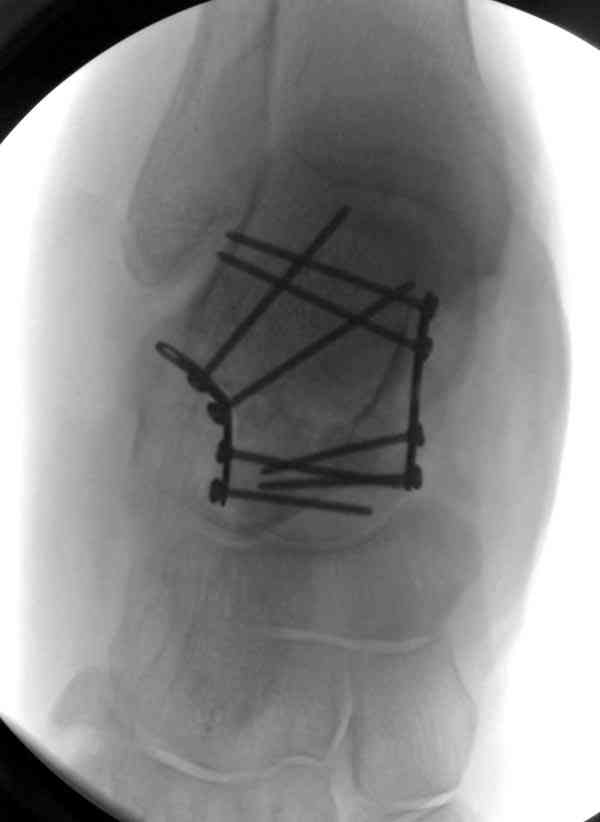

Случай с множественным оскольчатым переломом тарана оперированный из двойного доступа.

Через 2 мес.:

Через 8 мес.:

Через 14 мес.:

(кстати, на нашем случае была применена костная пластика-allograft crouton для заполнения дефектов)